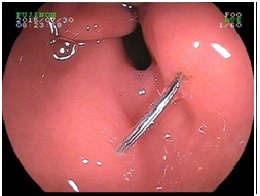

食物相关的异物:各种骨头、鱼刺、虾蟹贝的壳、枣核等尖锐的果核、坚果的果皮、大块没有嚼烂的食物等等,这一目录里的东西,大多数细嚼慢咽是不会误吞的。一些地区的饮食习俗也需要注意,如北方过年包饺子喜欢在里面放硬币,虽说寓意吉利,但吞进肚子或者硌坏牙齿的事故时有发生;南方的鱼丸、鱼糕等食品,制作时有时鱼骨难以完全去净,吃的时候还需要小心;喜欢煲汤的朋友们,处理食材时不要剁得过碎,喝汤时最后几口也是最容易卡到碎骨头的时候,而且这个时候一般已经吃饱喝足,来到医院胃镜是没法当时做的,需要等胃排空,只好整夜待在医院里留观,苦不堪言。在外面吃饭时更要小心,例如烤串的竹签劈裂下来的木刺、面条里的刷锅用的钢丝球、盒饭里方便饭盒掉下来的塑料片等等,这些都是真实发生过的教训。食物没有嚼烂卡在食管里的情况一般老年人相对多见,因为食物是可以消化的,可以尝试用胃镜把食团轻轻推进胃里。但是要注意,如果您平时细嚼慢咽,还是总觉得食物会卡住,一定要做个胃镜或钡餐检查一下,明确是不是食管本身出了问题。

图(3)食管内的鱼骨,横在管腔内,后图是取出来的鱼骨